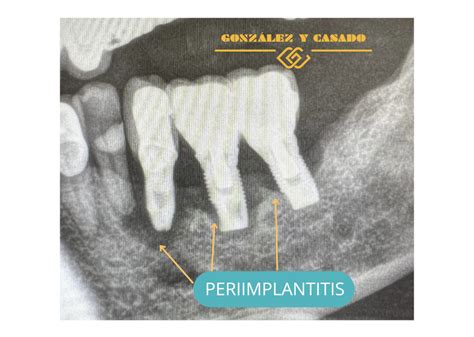

- Radiografías dentales: La confirmación de la periimplantitis suele requerir radiografías, típicamente radiografías periapicales o panorámicas de la zona del implante. En la radiografía buscamos evidencias de pérdida ósea alrededor del implante comparado con radiografías tomadas justo después de colocarlo. Un signo típico es un cráter o sombra alrededor de la rosca del implante indicando que el hueso se ha reabsorbido. Si disponemos de radiografías anteriores, podemos determinar cuánto hueso se ha perdido con el tiempo. Incluso una pérdida ósea mínima (por ejemplo 2-3 mm) acompañada de inflamación nos haría diagnosticar periimplantitis incipiente.

Un aspecto del diagnóstico es determinar si el caso es solo mucositis (encía inflamada pero hueso intacto) o ya es periimplantitis (con pérdida ósea). Esto se clarifica combinando el sondeo y la radiografía. Si hay sangrado al sondeo pero la radiografía muestra el hueso intacto, hablaríamos de mucositis periimplantaria. En cambio, si la radiografía muestra periimplante con pérdida ósea (por ejemplo se ven expiras del implante descubiertas) junto con inflamación clínica, entonces es periimplantitis.